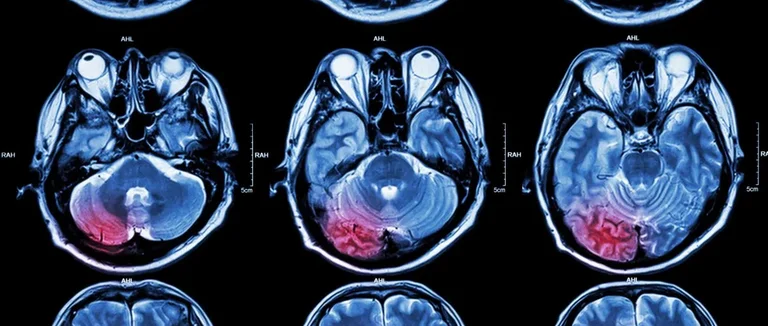

L'IRM Cérébrale pour le Cancer : Gold Standard du Diagnostic

L'imagerie par résonance magnétique (IRM) est essentielle pour diagnostiquer les tumeurs cérébrales. Elle est plus précise que d'autres méthodes. Voyons comment elle fonctionne et ses avantages.

Principes Fondamentaux de l'Imagerie par Résonance Magnétique

L'IRM utilise un fort champ magnétique et des ondes radio pour créer des images détaillées du cerveau. Cela aide à voir les tissus mous avec précision. C'est crucial pour trouver les tumeurs cérébrales.

Le fonctionnement de l'IRM repose sur l'alignement des protons dans les tissus du corps sous l'effet du champ magnétique. Lorsque les ondes radio sont appliquées, ces protons émettent des signaux. Ces signaux sont captés par l'appareil pour créer des images.

Avantages de l'IRM par Rapport aux Autres Méthodes d'Imagerie

L'IRM a des avantages par rapport à la TDM et à la TEP. Elle offre une meilleure visualisation des structures cérébrales et des tumeurs.

● Haute résolution des images des tissus mous

● Possibilité de détecter les tumeurs à un stade précoce

● Meilleure caractérisation des tumeurs grâce aux différentes séquences d'IRM

Ces avantages rendent l'IRM la meilleure option pour diagnostiquer et suivre les tumeurs cérébrales.

Processus de Détection des Tumeurs Cérébrales par IRM

L'IRM aide à voir les tissus du cerveau en détail. Cela permet aux médecins de diagnostiquer précisément.

Visualisation Détaillée des Tissus Cérébraux

L'IRM utilise des champs magnétiques puissants pour créer des images claires du cerveau. Cette méthode aide à voir les structures cérébrales en détail. Cela aide à détecter les anomalies, comme les tumeurs.

Les images IRM montrent la taille, la forme et l'emplacement des tumeurs. Ces détails sont essentiels pour choisir le meilleur traitement.